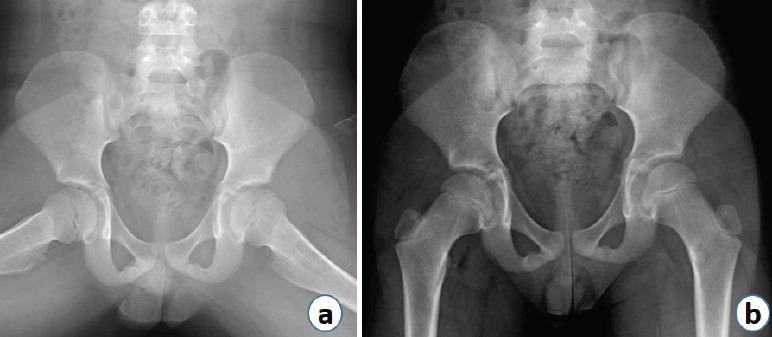

A 7-year-old male presented with complaints of hip pain and inability to bear weight. X-rays revealed Brodie's abscess in the proximal femur which was initially misdiagnosed as toxic synovitis with an incidental unicameral bone cyst (UBC).